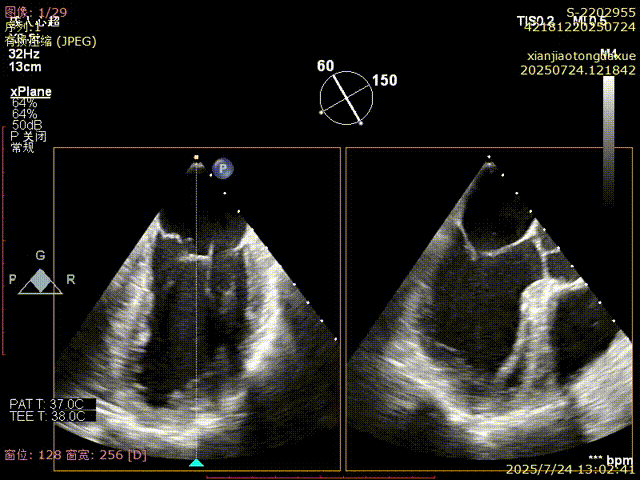

影像评估提示病变位于二尖瓣三区交界,瓣膜结构复杂,患者低氧血症,无法耐受体外循环,传统外科修复风险高,微创TEER治疗成为优选方案。手术团队采用ValveClamp® II型夹进行精准定位与夹合。通过麻醉快速通道迅速、高效完成手术,术中经经食道超声(TEE)实时引导,夹子精准落点于三区交界,瓣叶抓取稳定,夹合线条自然,反流显著改善,术后即刻拔除气管 ,插管,术后无并发症,心功能恢复良好。

捕获瓣叶并进行夹合